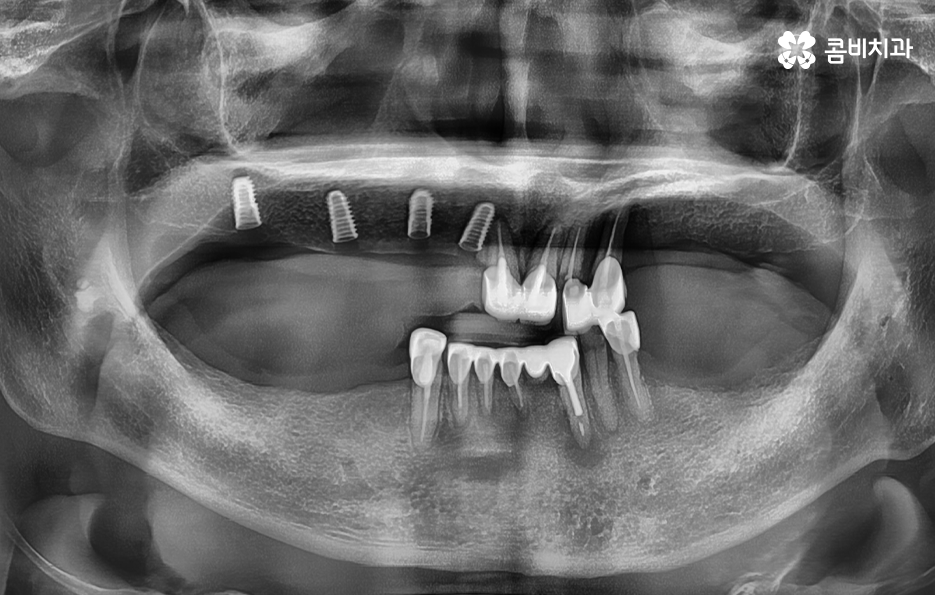

실제 치료 사례를 살펴보더라도 젊은 환자분들의 경우 원데이임플란트로도 치료가 가능한 사례가 많다면 노인분들의 경우 잇몸이 약해진 상태에서 치주염으로 치아를 잃게 된 경우가 많다보니 뼈이식을 추가적으로 받아야 하는 경우가 많이 있어요

임플란트의 치료 과정에서 중요한 부분은 잇몸 뼈에 임플란트 인공치근을 식립하여 골유착 과정을 안전하게 거쳐야 하기 때문에 잇몸 뼈의 중요성이 그만큼 크다고 할 수 있는데요

5,60대 이후 환자 분들의 경우에는 잇몸 상태가 이미 좋지 않은 분들이 많고 전신질환이 있는 분들도 많기 때문에 임플란트 나이에 있어서는 보다 섬세한 치료가 필요한 경우가 좀더 많다고 볼 수 있어요